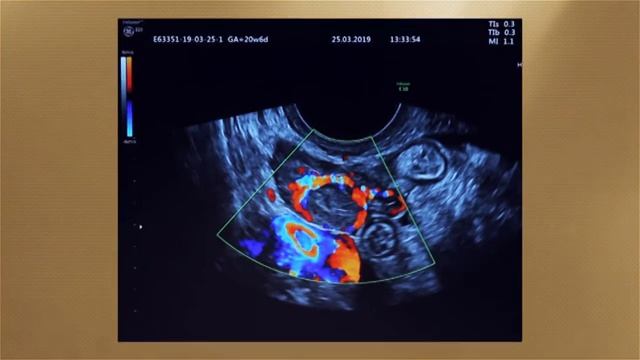

УЗИ МАТКИ И ПРИДАТКОВ

Видео